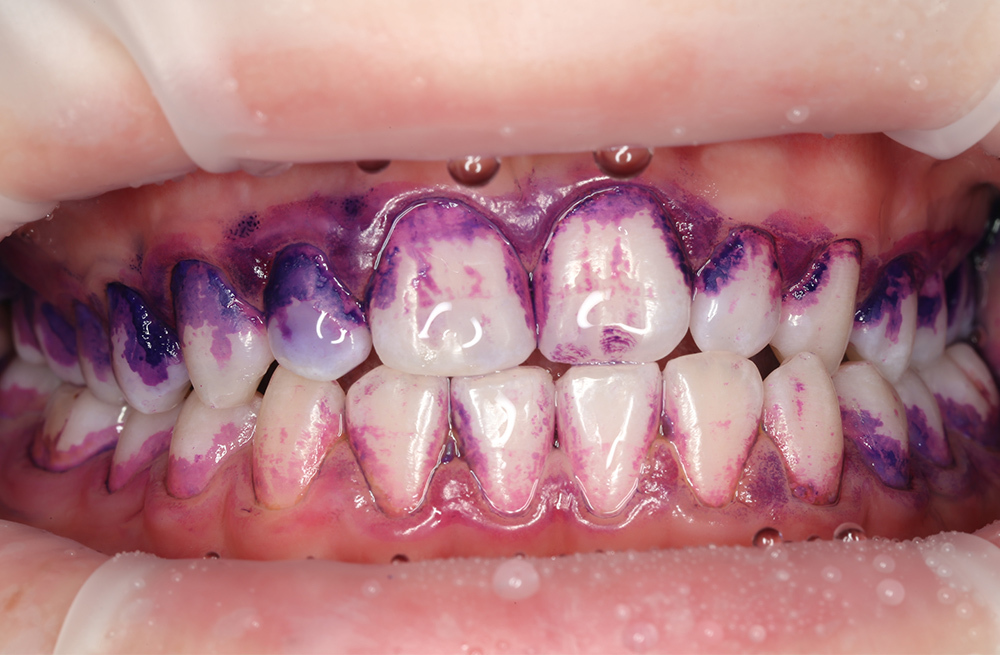

Удаление мягкого и пигментированного налёта у подростка с использованием Air-flow